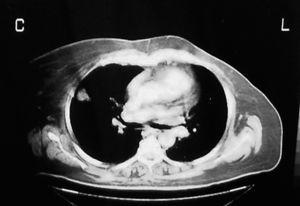

De las cuatro restantes tumoraciones infraescapulares estudiadas, reflejadas en la tabla 1, dos fueron liposarcomas, una fue un lipoma intramuscular y, la última, un hematoma asociado a rotura muscular. En todas ellas se planteó el ED como diagnóstico diferencial. En el caso 6 se halló una tumoración subescapular de unos 10 cm de diámetro en el contexto del estudio de una masa en el muslo derecho, cuya PAAF previa fue indeterminada, y que finalmente correspondió a un liposarcoma multicéntrico metastásico (fig. 7). El caso 7 correspondió a una masa escapular como diseminación de un liposarcoma mixoide en muslo (fig. 8). En el caso 8 se planteó el diagnóstico de elastofibroma por sus características clínicas, descartándolo tras una RMN y llegando al diagnóstico definitivo de lipoma intramuscular tras la resección (fig. 9). El caso 9 corresponde a un varón joven que presentaba una tumoración blanda y elástica en región subescapular de unos 5 cm de diámetro, de tres semanas de evolución y que molestaba con la tos. El estudio por ecografía fue suficiente para llegar al diagnóstico de ruptura muscular y hematoma secundario.

Figura 7. Masa subescapular cuyo diagnóstico final fue de liposarcoma multicéntrico metastásico.

Figura 8. Diseminación escapular de un liposarcoma mixoide en muslo.